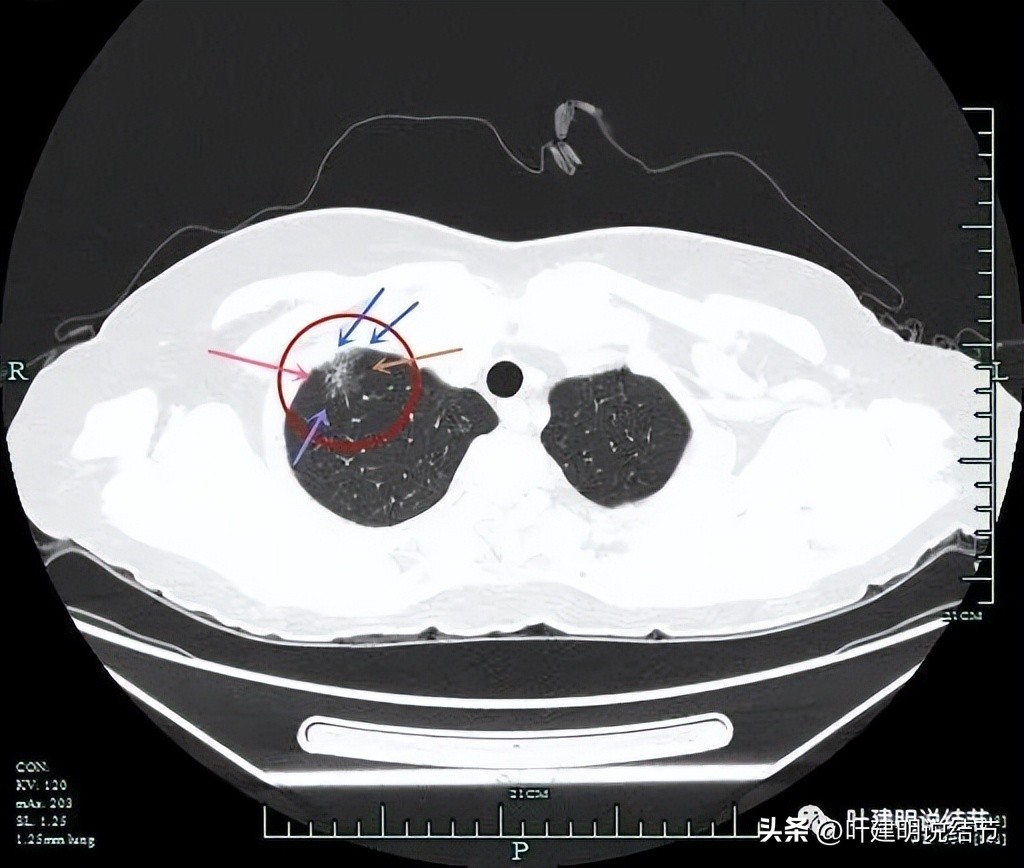

确实有实性成分,而且与胸壁间隙不清,而磨玻璃部分轮廓与瘤肺边界都比较清楚

病灶表面不平(砖色箭头);有实性成分(粉色箭头);连缘有毛刺(紫色箭头);整体瘤肺边界清(红色箭头)。

病灶与胸壁间没有间隙(蓝色箭头),余仍见表面不平以及毛刺征与瘤肺边界清楚等征象。